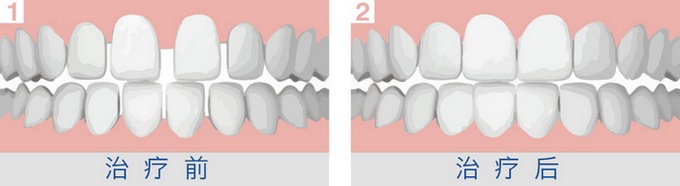

牙间隙矫正会痛吗?牙齿稀疏影响个人气质,谈笑间无疑会给个人形象减分不少。很多患者都想到通过矫正来修复牙间隙,但又很担心会疼痛,也就对矫正望而却步。牙间隙矫正真的会痛吗?下面我们一起来看看医生的介绍。

大连康贝佳矫正医生指出,牙齿矫正是借助外力是牙齿缓慢移动,初期两三天有疼痛不适感是正常的,疼痛也是在患者能够忍受的范围之内。

传统正畸方法通过钢丝矫正,也就是我们常说的牙套。采用牙套技术矫正牙齿通常需要2年左右的时间,每一个月左右需要进行检查,调节钢丝力度,让锁槽越来越小,越来越光滑,改进正畸治疗弓丝,使之能产持续、柔和的矫治力。一般每次复诊、弓丝加力后,会有2-3天的不适感。刚戴上牙套的人们会很不习惯,容易磨损嘴皮,钢丝的拉力拉动牙根,有疼痛感,不过很快就会适合或者消失。

当然牙齿稀疏矫正疼痛感与患者个人的耐受力也有关。每个人戴上牙箍之后的感觉是不一样的,有的爱美者会觉得疼,而有的爱美者则没什么感觉。其实在第一次矫正时,出现胀、咬物不适等不适感都是正常的,说明牙齿矫正器正起到作用。